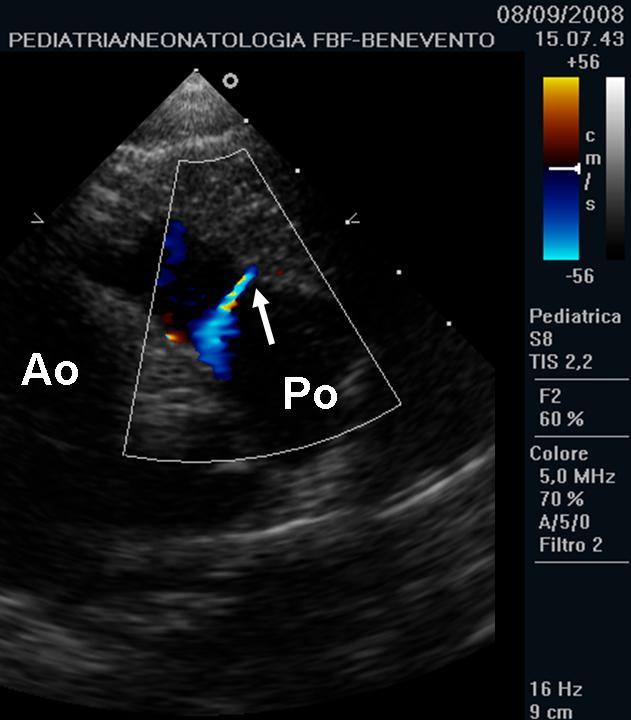

Ecocardiografiacolor-Doppler � tra le indagini strumentali pi�

fistoloso, entit� di shunt; Figura 2), per

Figura

2. Immagine ecocardiografica, proiezione parasternale asse corto,

alta. La freccia indica lo sbocco della fistola sulla parete laterale

del tronco polmonare. Ao, aorta. Po, tronco polmonare.